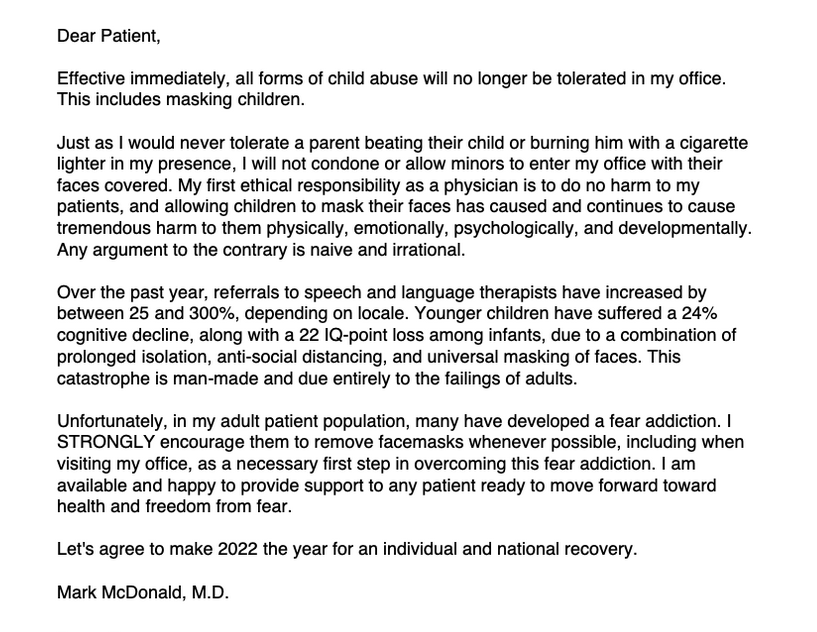

Psychiatrist Mark McDonald, M.D., author of United States of Fear: How America Fell Victim to a Mass Delusional Psychosis, sent a letter to his patients in February banning child masking in his practice. Forcing kids to mask, he says, is child abuse.

“My first ethical responsibility as a physician is to do no harm to my patients, and allowing children to mask their faces has caused and continues to cause tremendous harm to them physically, emotionally, psychologically and developmentally. Any argument to the contrary is naive and irrational.”

“Masks… may not leave physical scars (although they often result in painful skin infections that can lead to permanent facial disfigurement),” says Dr. McDonald, “but they do cause significant and possibly permanent damage to a child’s brain, retarding speech and language development, crippling social skills, and inciting a vicious cycle of emotional dysregulation leading to major depression, self-harm, and substance abuse. We would never allow someone to do this to our children directly, so why do we condone it through the vehicle of a facemask?”

In his post, Masking Children is Child Abuse, psychiatrist McDonald adds:

“Since children began wearing masks at school, on the athletic field, in airplanes—essentially everywhere outside the home—I have seen a significant decline in their ability to make eye contact, speak clearly, and initiate face-to-face communication with other human beings. Emotional resilience has dramatically declined. Children have become dull and slow in their thinking.”

Dr. McDonald notes that many adults in his psychiatric practice are beyond anxious, they are literally addicted to hiding behind face coverings:

“In my adult patient population, many have developed a fear addiction. I strongly encourage them to remove facemasks whenever possible, including when visiting my office, as a necessary first step in overcoming this fear addiction.”